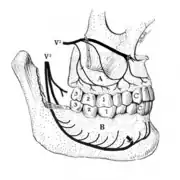

A tooth is composed of an outer shell of calcified hard tissues (from hardest to softest: enamel, dentin, and cementum), and an inner soft tissue core (the pulp system), which contains nerves and blood vessels. The visible parts of the teeth in the mouth – the crowns (covered by enamel) – are anchored into the bone by the roots (covered by cementum). Underneath the cementum and enamel layers, dentin forms the bulk of the tooth and surrounds the pulp system. The part of the pulp inside the crown is the pulp chamber, and the central soft tissue nutrient canals within each root are root canals, exiting through one or more holes at the root end (apical foramen/foramina). The periodontal ligament connects the roots to the bony socket. The gingiva covers the alveolar processes, the tooth-bearing arches of the jaws.[45]: 1–5